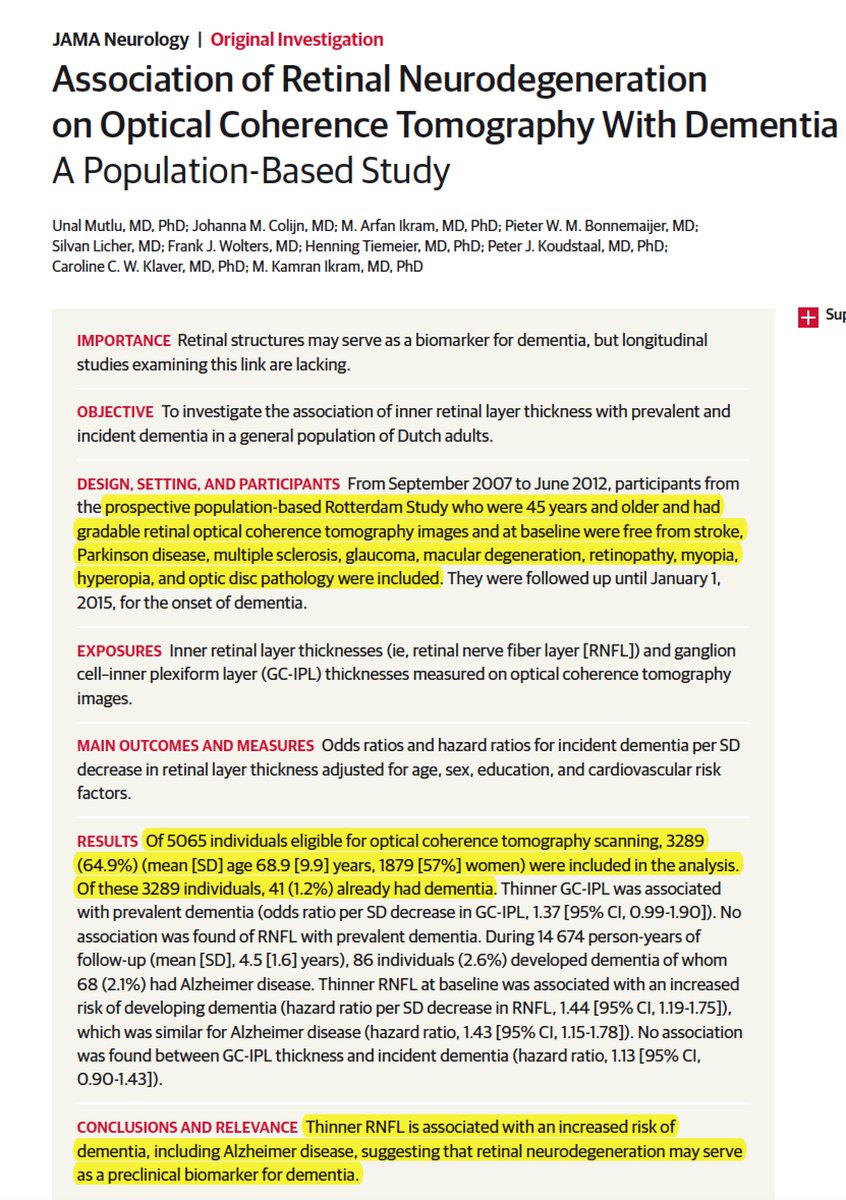

JAMAOphthalmology Retweeted

Retweeted from Eric Topol: Will your eye OCT exams be a window to cognitive decline in the future? https://jamanetwork.com/journals/jamaneurology/fullarticle/2685869 …

@JAMANeuro@erasmusuni@erasmusmc pic.twitter.com/tfPig520AB#medicinepic.twitter.com/ieniCNQoKh